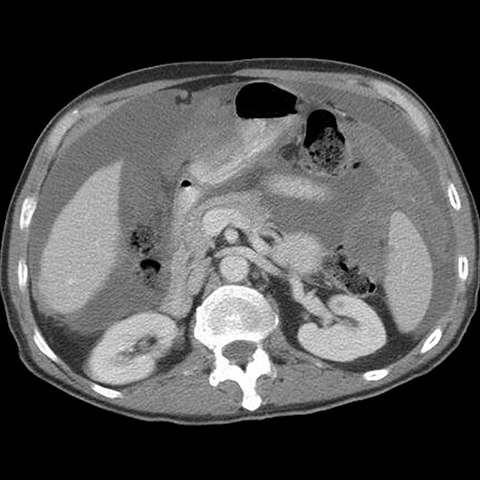

77 year-old woman with a history of ovarian cancer presents with increasing abdominal girth. [4 of 6]